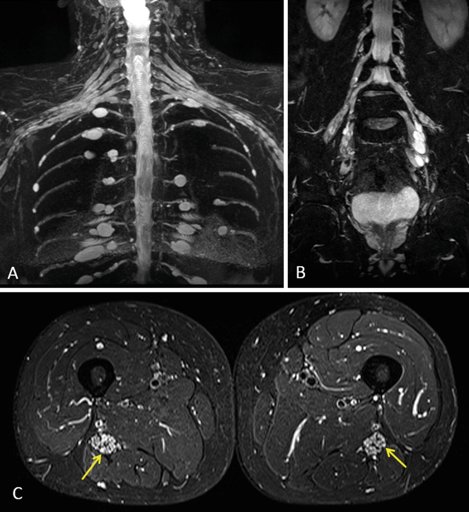

Chụp cộng hưởng từ dây thần kinh ngoại biên

Chụp cộng hưởng từ (MRI) dây thần kinh ngoại biên là một phương pháp chẩn đoán hình ảnh tiên tiến, hiện đại trong chẩn đoán các bệnh lý về dây thần kinh ngoại biên. Giá trị của chụp cộng hưởng từ dây thần kinh ngoại biên là vô cùng lớn giúp các bác sĩ rất nhiều trong việc chẩn đoán và điều trị bệ...